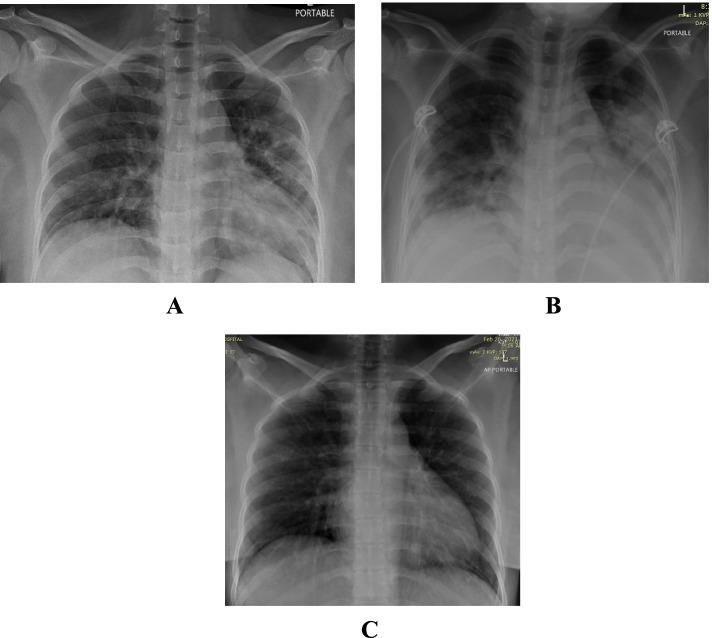

This is a retrospective case series study. We have included seven pregnant women admitted with early COVID-19 infection to a tertiary care hospital, Latifa Maternity Hospital in Dubai, United Arab Emirates between 12 February and 04 March 2021 and who consented to receive COVID-19 convalescent plasma as part of their treatment plan. Main outcomes measured were clinical and radiological features, laboratory tests, WHO clinical progression scale pre and post treatment, and maternal, fetal outcomes. COVID-19 clinical severity was classified according to the NIH guidelines for criteria of SARS-CoV-2. For the radiological features, a modified chest X-ray scoring system was used where each lung was divided into 6 zones (3 on each side upper, middle, and lower). Opacities were classified into reticular, ground glass, patchy and dense consolidations patterns.

这是一项回顾性病例系列研究。我们纳入了 2021 年 2 月 12 日至 3 月 4 日期间在阿拉伯联合酋长国迪拜拉蒂法妇产医院因早期 COVID-19 感染住院且同意接受 COVID-19 恢复期血浆治疗的 7 名孕妇。主要观察指标为临床和影像学特征、实验室检查、治疗前后世界卫生组织临床进展量表(WHO 临床进展量表)以及母婴结局。根据 NIH 指南,COVID-19 临床严重程度分为 SARS-CoV-2 标准。对于影像学特征,使用改良的胸部 X 线评分系统,每个肺分为 6 个区(每侧上、中、下各 3 个区)。将不透明性分为网状、磨玻璃、斑片状和致密性实变。